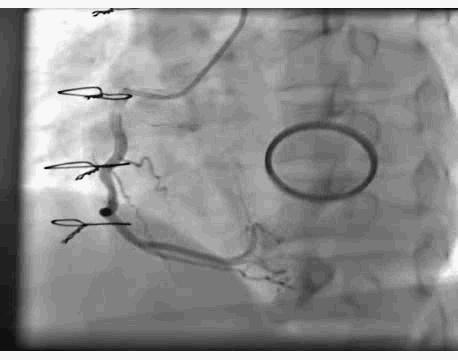

冠脉造影显示:左主干未见明显异常,前降支近中段动脉硬化,未见明显狭窄及血栓,远端血流TIMI 3级,回旋支全程可见散在斑块,近段局限性狭窄约50%,远段血栓影消失,远端前向血流TIMI 3级。

右冠脉动脉硬化,近中段可见多处局限性斑块病变轻度狭窄,远端血流TIMI 3级。 结论:符合冠心病、急性心肌梗死改变,目前回旋支远段血栓自溶,未见明显狭窄病变,暂不予以支架植入。

主要造影结果

月经期结束后复查冠脉造影显示,回旋支远段血栓影消失,远端前向血流TIMI 3级。

回旋支远段血栓自溶,考虑为抗凝、抗血小板作用及患者月经期凝血状态、雌激素水平改变共同影响。处于月经期女性发生急性心肌梗死,若病情平稳应如何处理,目前指南并没有明确推荐。